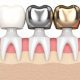

راهکار درمانی دیگر که در موارد شدیدتر به کار گرفته می شود، استفاده از روکش یا ونیر دندان و همچنین تاج دندان است.. این ابزارها توسط متخصص دندانپزشکی ترمیمی و زیبایی استفاده میشود تا از پوسیدگی بیشتر آن جلوگیری کند.

با توجه به اینکه ما انسانها در طول زندگی خود با انواع خوراکی های اسیدی و شیمیایی در ارتباط هستیم، احتمال از بین رفتن مینای دندان وجود دارد که تحت عنوان فرسایش مینای دندان یا تحلیل مینای دندان شناخته می شود. با توجه به اینکه مینای دندان بافت زنده ندارد و احتمال ترمیم آن صفر است، روش هایی مانند ونیر دندان یا تاج دندان و همچنین پوشش دادن دندان با رزین و بهترین گزینه های درمانی هستند. حالا اگر شما احساس می کنید که بخش مهمی از مینای دندان خود را از دست داده اید و به فکر درمان آن هستید می توانید از طریق شماره های سایت با ما در تماس باشید و برای مشاوره بیشتر و رزرو وقت از آن استفاده کنید.